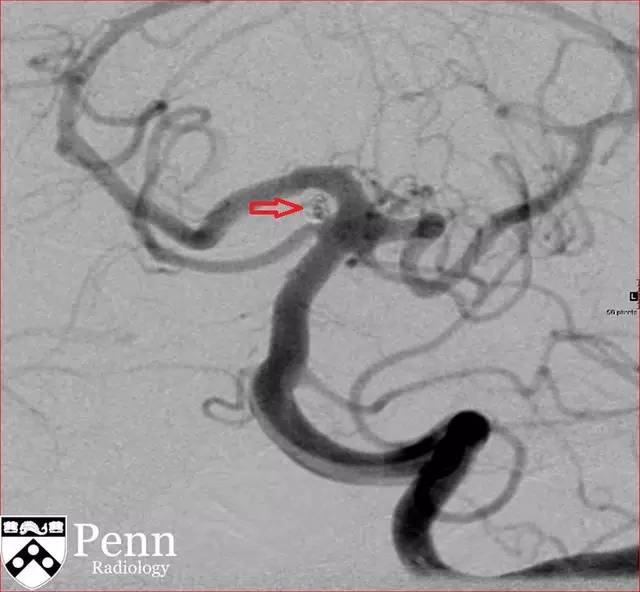

图 4 DSA 可见囊样动脉瘤(红色箭头)

DSA:是诊断血管病变的金标准,具有非常高的空间分辨率和时间分辨率。可在动脉分叉处看到囊状影。破裂部位常可看到「墨菲乳头」。